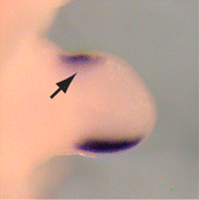

Preaxial polydactyly

The condition has an incidence of 1 in every 500 live births. Postaxial hand polydactyly is a common isolated disorder in African black children, and autosomal dominant transmission is suspected. Postaxial polydactyly is more frequent in native Africans living in the Eastern and Central than the Caucasians and Mongoloids and is more frequent in male children.[40] In contrast, postaxial polydactyly seen in white children is usually syndromic and associated with an autosomal recessive transmission. One study by Finley et al. combined data from Jefferson County, Alabama, United States and Uppsala County, Sweden. This study showed incidence of all types of polydactyly to be 2.3 per 1000 in Caucasian males, 0.6 per 1000 in Caucasian females, 13.5 per 1000 in African males, and 11.1 per 1000 in African females.[29]